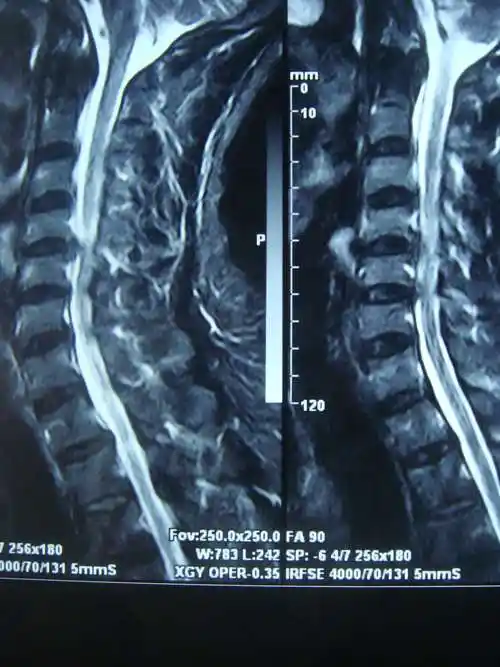

颈椎ct示:颈4-5骨赘增生严重颈椎侧位片示:颈椎生理曲度消失,反弓术中

术前ct示c6/7椎体增生伴椎间孔狭窄

颈椎ct提示颈4-5,5-6椎间盘突出,后纵韧带钙化

颈椎ct三维提示:颈椎管狭窄,未见明显后纵韧带及黄韧带骨化.